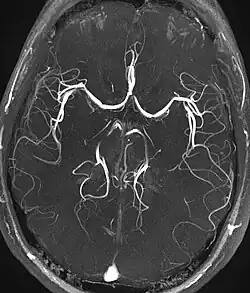

| Magnetic resonance angiography (MRA) and venography | Time-of-flight | TOF | Blood entering the imaged area is not yet magnetically saturated, giving it a much higher signal when using short echo time and flow compensation. | Detection of aneurysm, stenosis, or dissection[31] |

|

| Phase-contrast magnetic resonance imaging | PC-MRA | Two gradients with equal magnitude, but opposite direction, are used to encode a phase shift, which is proportional to the velocity of spins.[32] | Detection of aneurysm, stenosis, or dissection (pictured).[31] | ![]() (VIPR) |

Magnetic resonance angiography

Magnetic resonance angiography (MRA) is a group of techniques based to image blood vessels. Magnetic resonance angiography is used to generate images of arteries (and less commonly veins) in order to evaluate them for stenosis (abnormal narrowing), occlusions, aneurysms (vessel wall dilatations, at risk of rupture) or other abnormalities. MRA is often used to evaluate the arteries of the neck and brain, the thoracic and abdominal aorta, the renal arteries, and the legs (the latter exam is often referred to as a "run-off").

Phase contrast

Phase contrast MRI (PC-MRI) is used to measure flow velocities in the body. It is used mainly to measure blood flow in the heart and throughout the body. PC-MRI may be considered a method of magnetic resonance velocimetry. Since modern PC-MRI typically is time-resolved, it also may be referred to as 4-D imaging (three spatial dimensions plus time).[51]